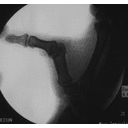

Stress Test Xray.jpg